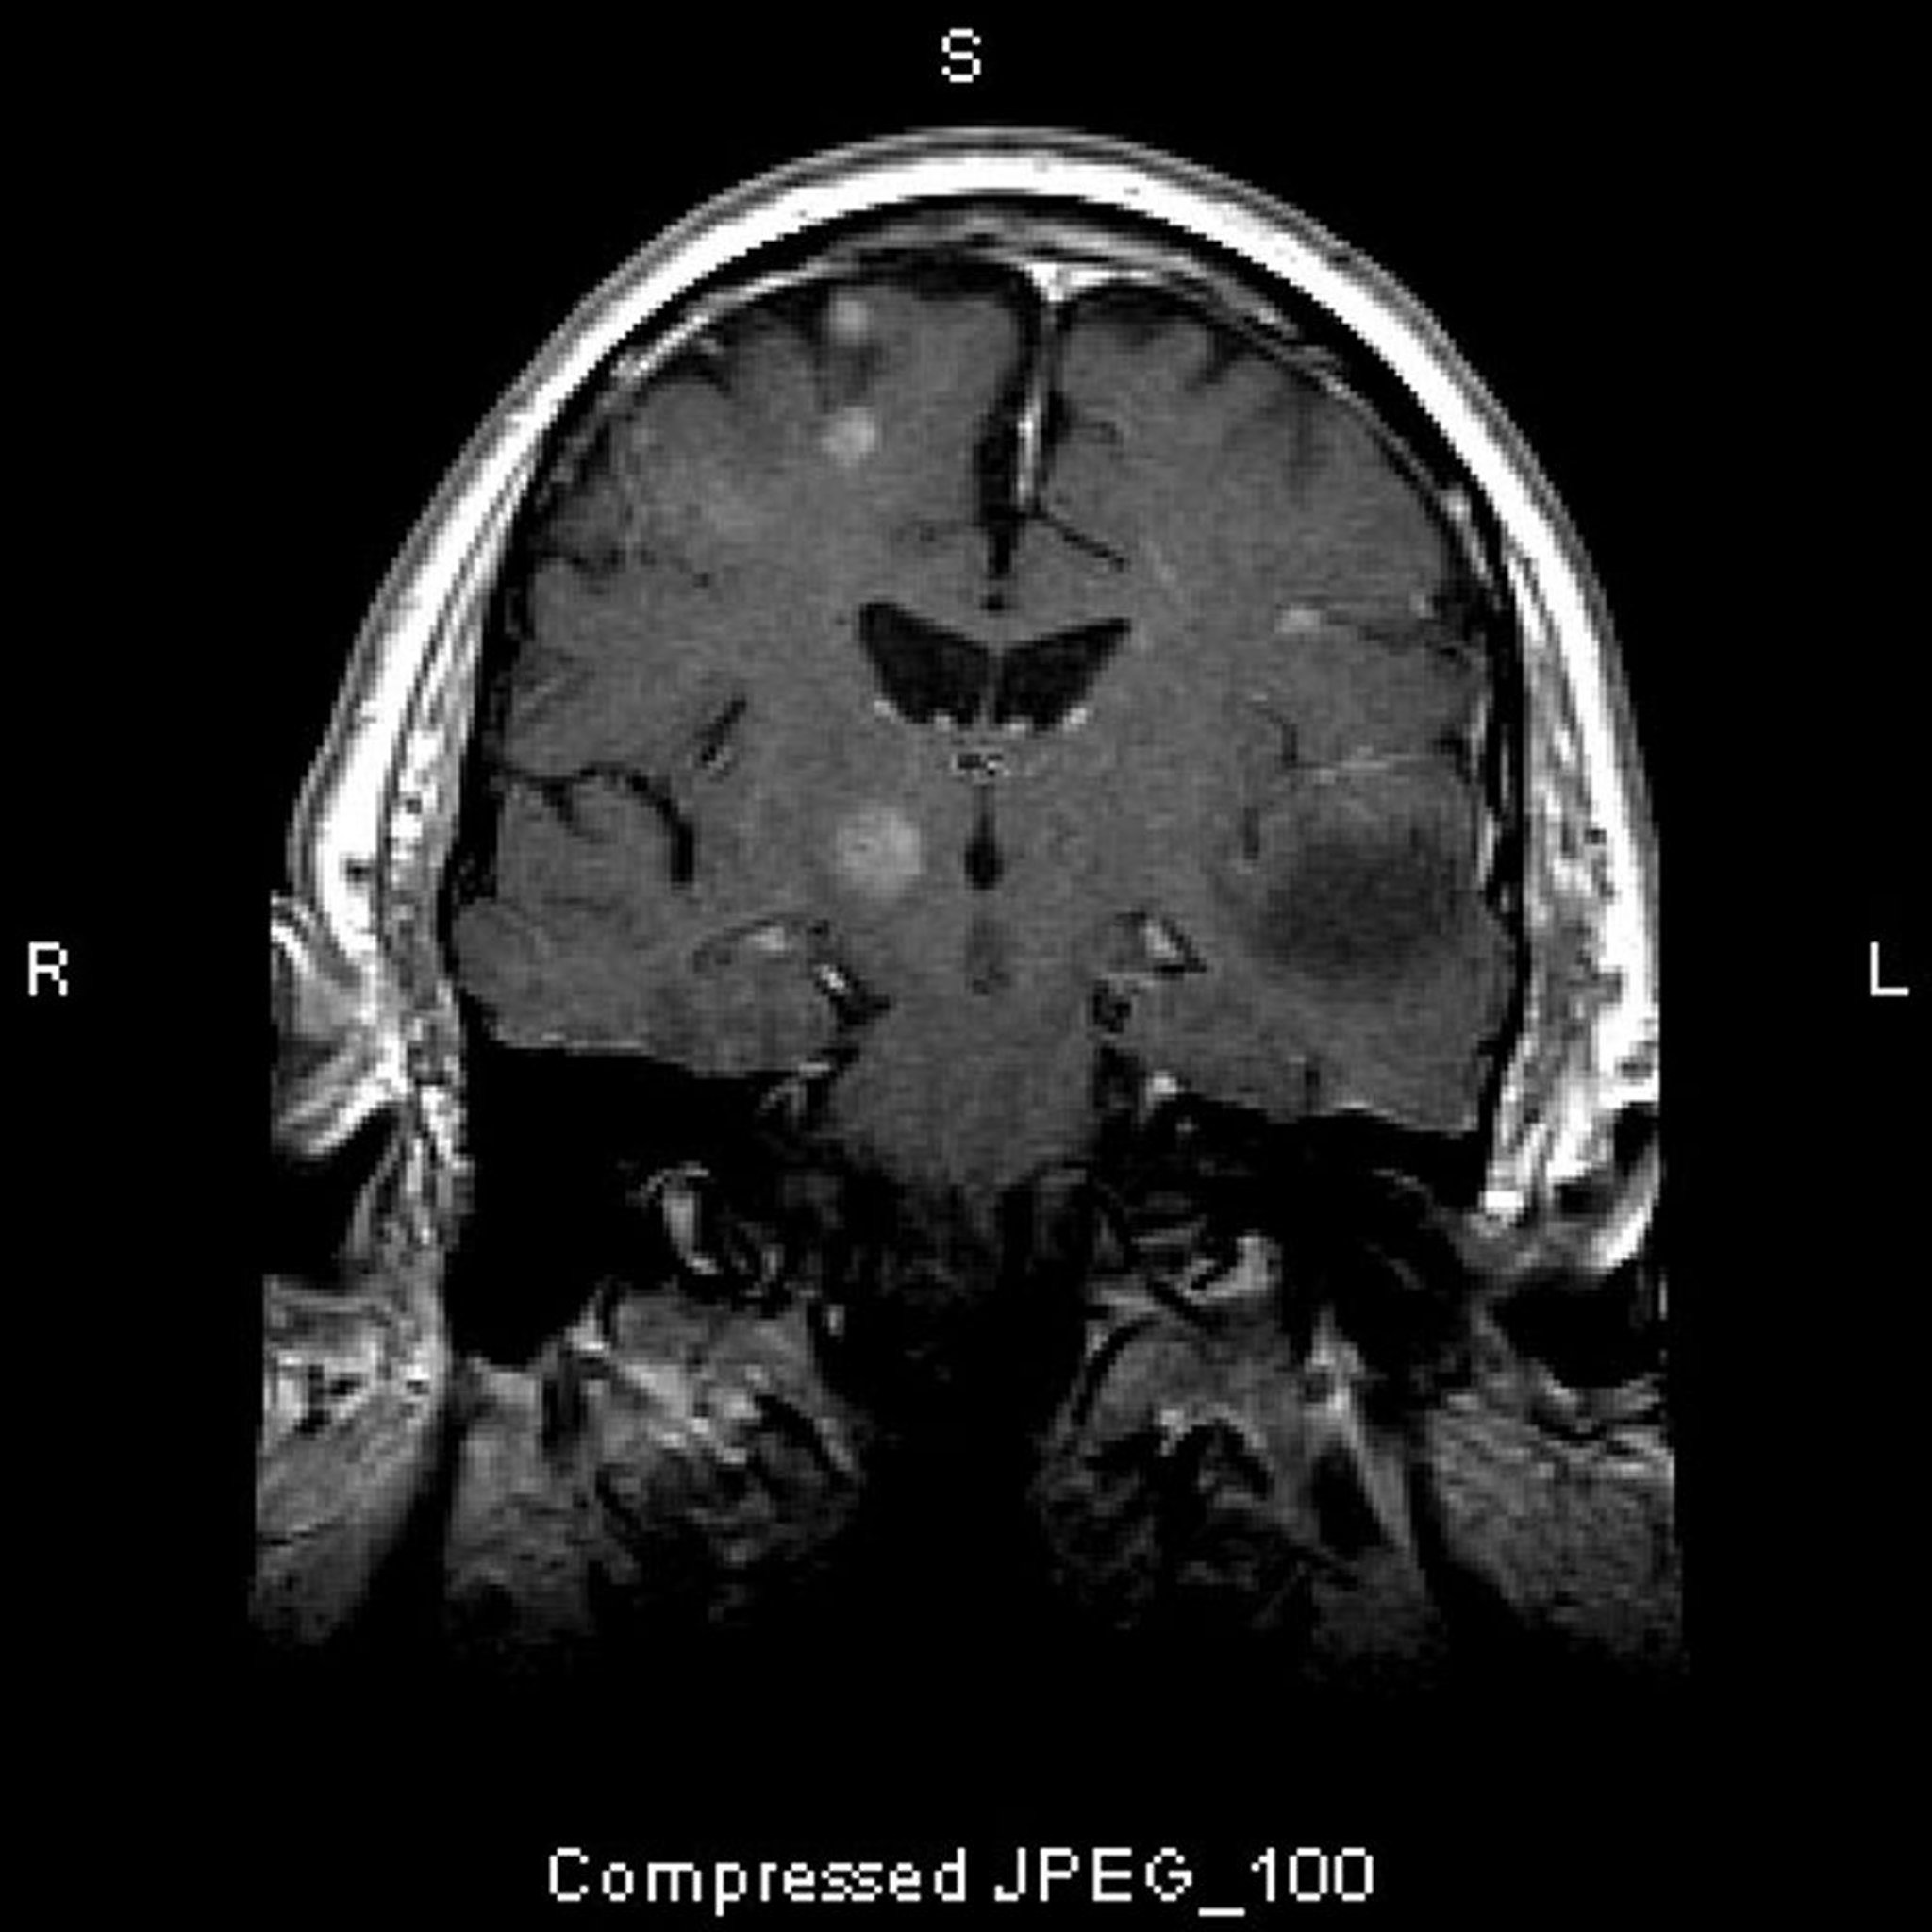

This MRI scan shows multiple brain lesions, representing metastatic tumors. Over 80% of brain metastases are multiple.

Image courtesy of William R. Shapiro, MD.